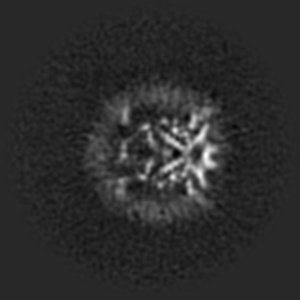

5.4 Denoising real data

In this section we test our method on real data from single-particle Cryo-Electron Microscopy (see Cheng et al., (2015) for an introduction), where many particles of the same type are suspended in liquid, frozen, and put under an electron microscope. This produces extremely noisy D-images which need to be refined before further steps like D reconstruction can be attempted. This presents an opportunity to investigate the performance of our method on practically relevant real world data with non-Gaussian noise. We use the EMPIAR- (Bacic et al.,, 2021) dataset of grayscale images with resolution. They were extracted from raw data and undergone some preprocessing, but are still very noisy (see Figure 8, top left). We trained a DDPM++ model555In order to compensate for the higher resolution we reduced the number of feature channels in the ddpmpp architecture from to , but otherwise used the same settings as for the synthetic data. Training took roughly hours on a two GPUs. on this data and used our method to generate samples (see Figure 8, right) whose shapes correspond strongly to what has been obtained by Bacic et al., (2021), see Figure 8, bottom. We emphasize that the network has only ever seen noisy data and has in no way been specifically adjusted based on a priori knowledge of these shapes. This can be seen by the fact that standard score inference generates noisy samples, very similar to those in the training set (see Figure 13 in the Appendix). The parameters used for Figure 8 of the extended score inference have been determined by hand with such knowledge, of course, but similar results are generated for a wide range of parameter choices (see Figure 12 in the Appendix). In particular, this demonstrates a significant capability of the extended score to guide generation towards samples from the underlying image manifold, also in the case of real data with extreme noise corruption caused by physical measurement modalities. This example serves as proof of concept for the validation of our approach: reaching state-of-the-art performance is outside the scope of this work, and would require incorporating more prior domain knowledge.